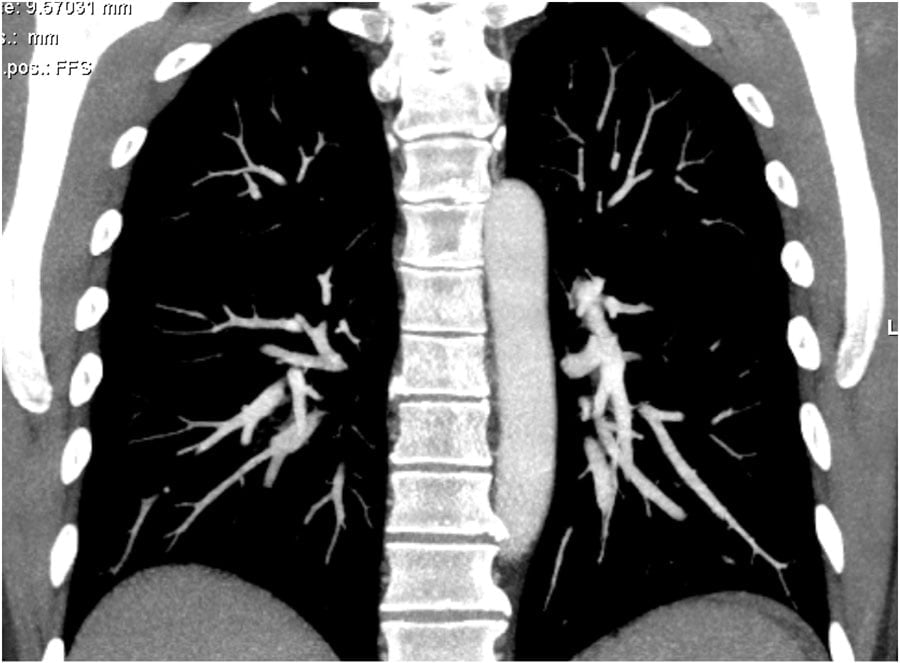

1. Optimal 2. Too late. 3. Transient interruption of contrast

1. Tối ưu; 2. Quá trễ; 3. Giảm chất tương phản thoáng qua

The quality of CT depends on good contrast delivery and perfect timing.

Scans for pulmonary emboli are frequently of poor quality in young patients and of good quality in old patients. The explanation is the following:

– Older patients usually have a poor cardiac output, which results in a compact contrast-bolus and good enhancement of the pulmonary vessels (see image 1).

– Young patients and especially pregnant women have a high cardiac output, which results in dilution of the contrast and poor enhancement.

– Young patients are capable of deeper inspiration, which can lead to transient interruption of contrast.

The images demonstrate:

1. Optimal enhancement of pulmonary arteries in an old patient with a poor cardiac output.

2. Poor enhancement of pulmonary arteries due to late scanning.

3. Good enhancement in SVC and aorta in image 3A, but insufficient enhancement of the pulmonary vessels due to TIC in image 3B.

Chất lượng phim CT động mạch phổi phụ thuộc vào kỹ thuật tiêm thuốc tương phản và chọn thời điểm chụp thích hợp.

Chụp thuyên tắc phổi thường có hình chất lượng kém ở bệnh nhân trẻ và có chất lượng tốt ở bệnh nhân già. Điều này được giải thích như sau:

– Bệnh nhân lớn tuổi thường có cung lượng tim thấp, dẫn đến một lượng lớn thuốc tương phản cô đặc lại và ngấm thuốc tốt ở các mạch phổi (hình 1).

– Các bệnh nhân trẻ và đặc biệt là phụ nữ mang thai có cung lượng tim cao, kết quả là pha loãng thuốc tương phản và ngấm thuốc kém.

– Bệnh nhân trẻ có khả năng hít sâu hơn, có thể dẫn đến hiện tượng giảm chất tương phản thoáng qua.

Biểu hiện trên hình ảnh:

1. Ngấm thuốc tối ưu ở các động mạch phổi ở bệnh nhân già có cung lượng tim thấp.

2. Ngấm thuốc của động mạch phổi kém do quét muộn.

3. Ngấm thuốc tốt trong SVC và động mạch chủ ở hình 3A, nhưng sự ngấm thuốc không đủ ở các mạch máu phổi do hiện tượng TIC trong hình 3B.